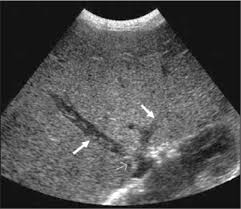

schistosomiasis